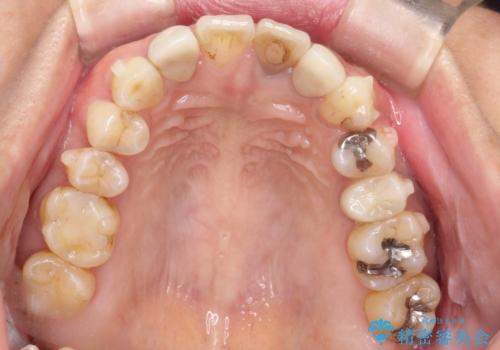

- 全体的なガタガタと前歯をきれいにしたいとのことで来院されました。

下の歯は重度のガタガタがあり、上の前歯は何本かが神経の治療がしてある状態でした。

インビザラインにて歯並びを整え、上顎の前歯にセラミックを装着する計画としました。